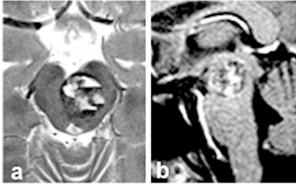

在神经外科领域,追求病变的完全切除常被视为金标准。然而,面对一位40岁的中脑海绵状血管瘤患者,INC国际神经外科大咖巴特朗菲教授及其团队做出了一个不一般的决定:应患者明确请求,...